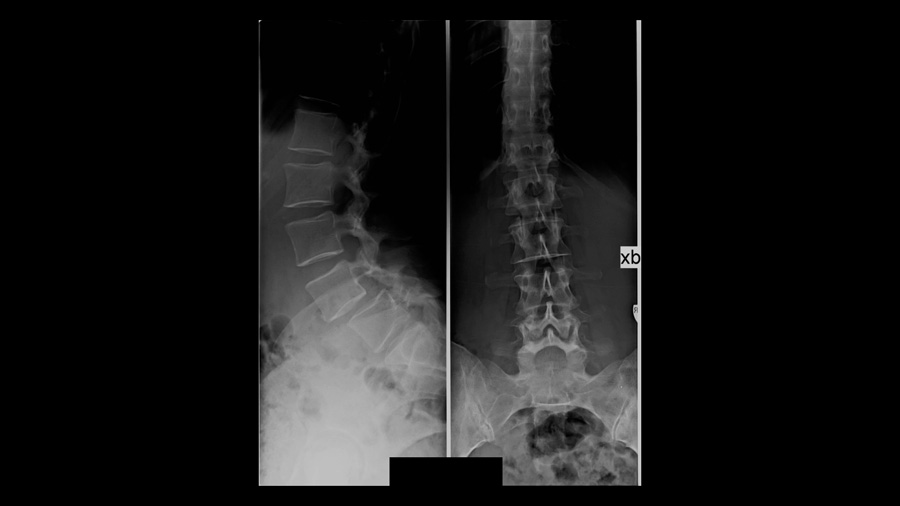

Standard radiographs demonstrated a degenerative spondylolisthesis at L4–5. Two decades ago, such a finding, especially when combined with correlating symptoms, would often have been enough to proceed directly to surgery, typically after confirming stenosis on MRI. Today, that approach is no longer considered sufficient for many patients.

Flexion–extension radiographs were obtained, not primarily to quantify motion at the index level, but to screen for potential instability at adjacent segments. While their utility remains controversial, they can occasionally reveal translation at levels not otherwise suspected.

More importantly, a full spine standing radiograph from C2 to the proximal femur was obtained in a standardized, relaxed position. This provided the basis for sagittal alignment analysis. Among all measured parameters, two stood out as particularly relevant:

In this patient, the pelvic incidence measured approximately 75°, placing her at the very high end of the spectrum. High PI fundamentally increases the biomechanical demand on the lumbar spine.